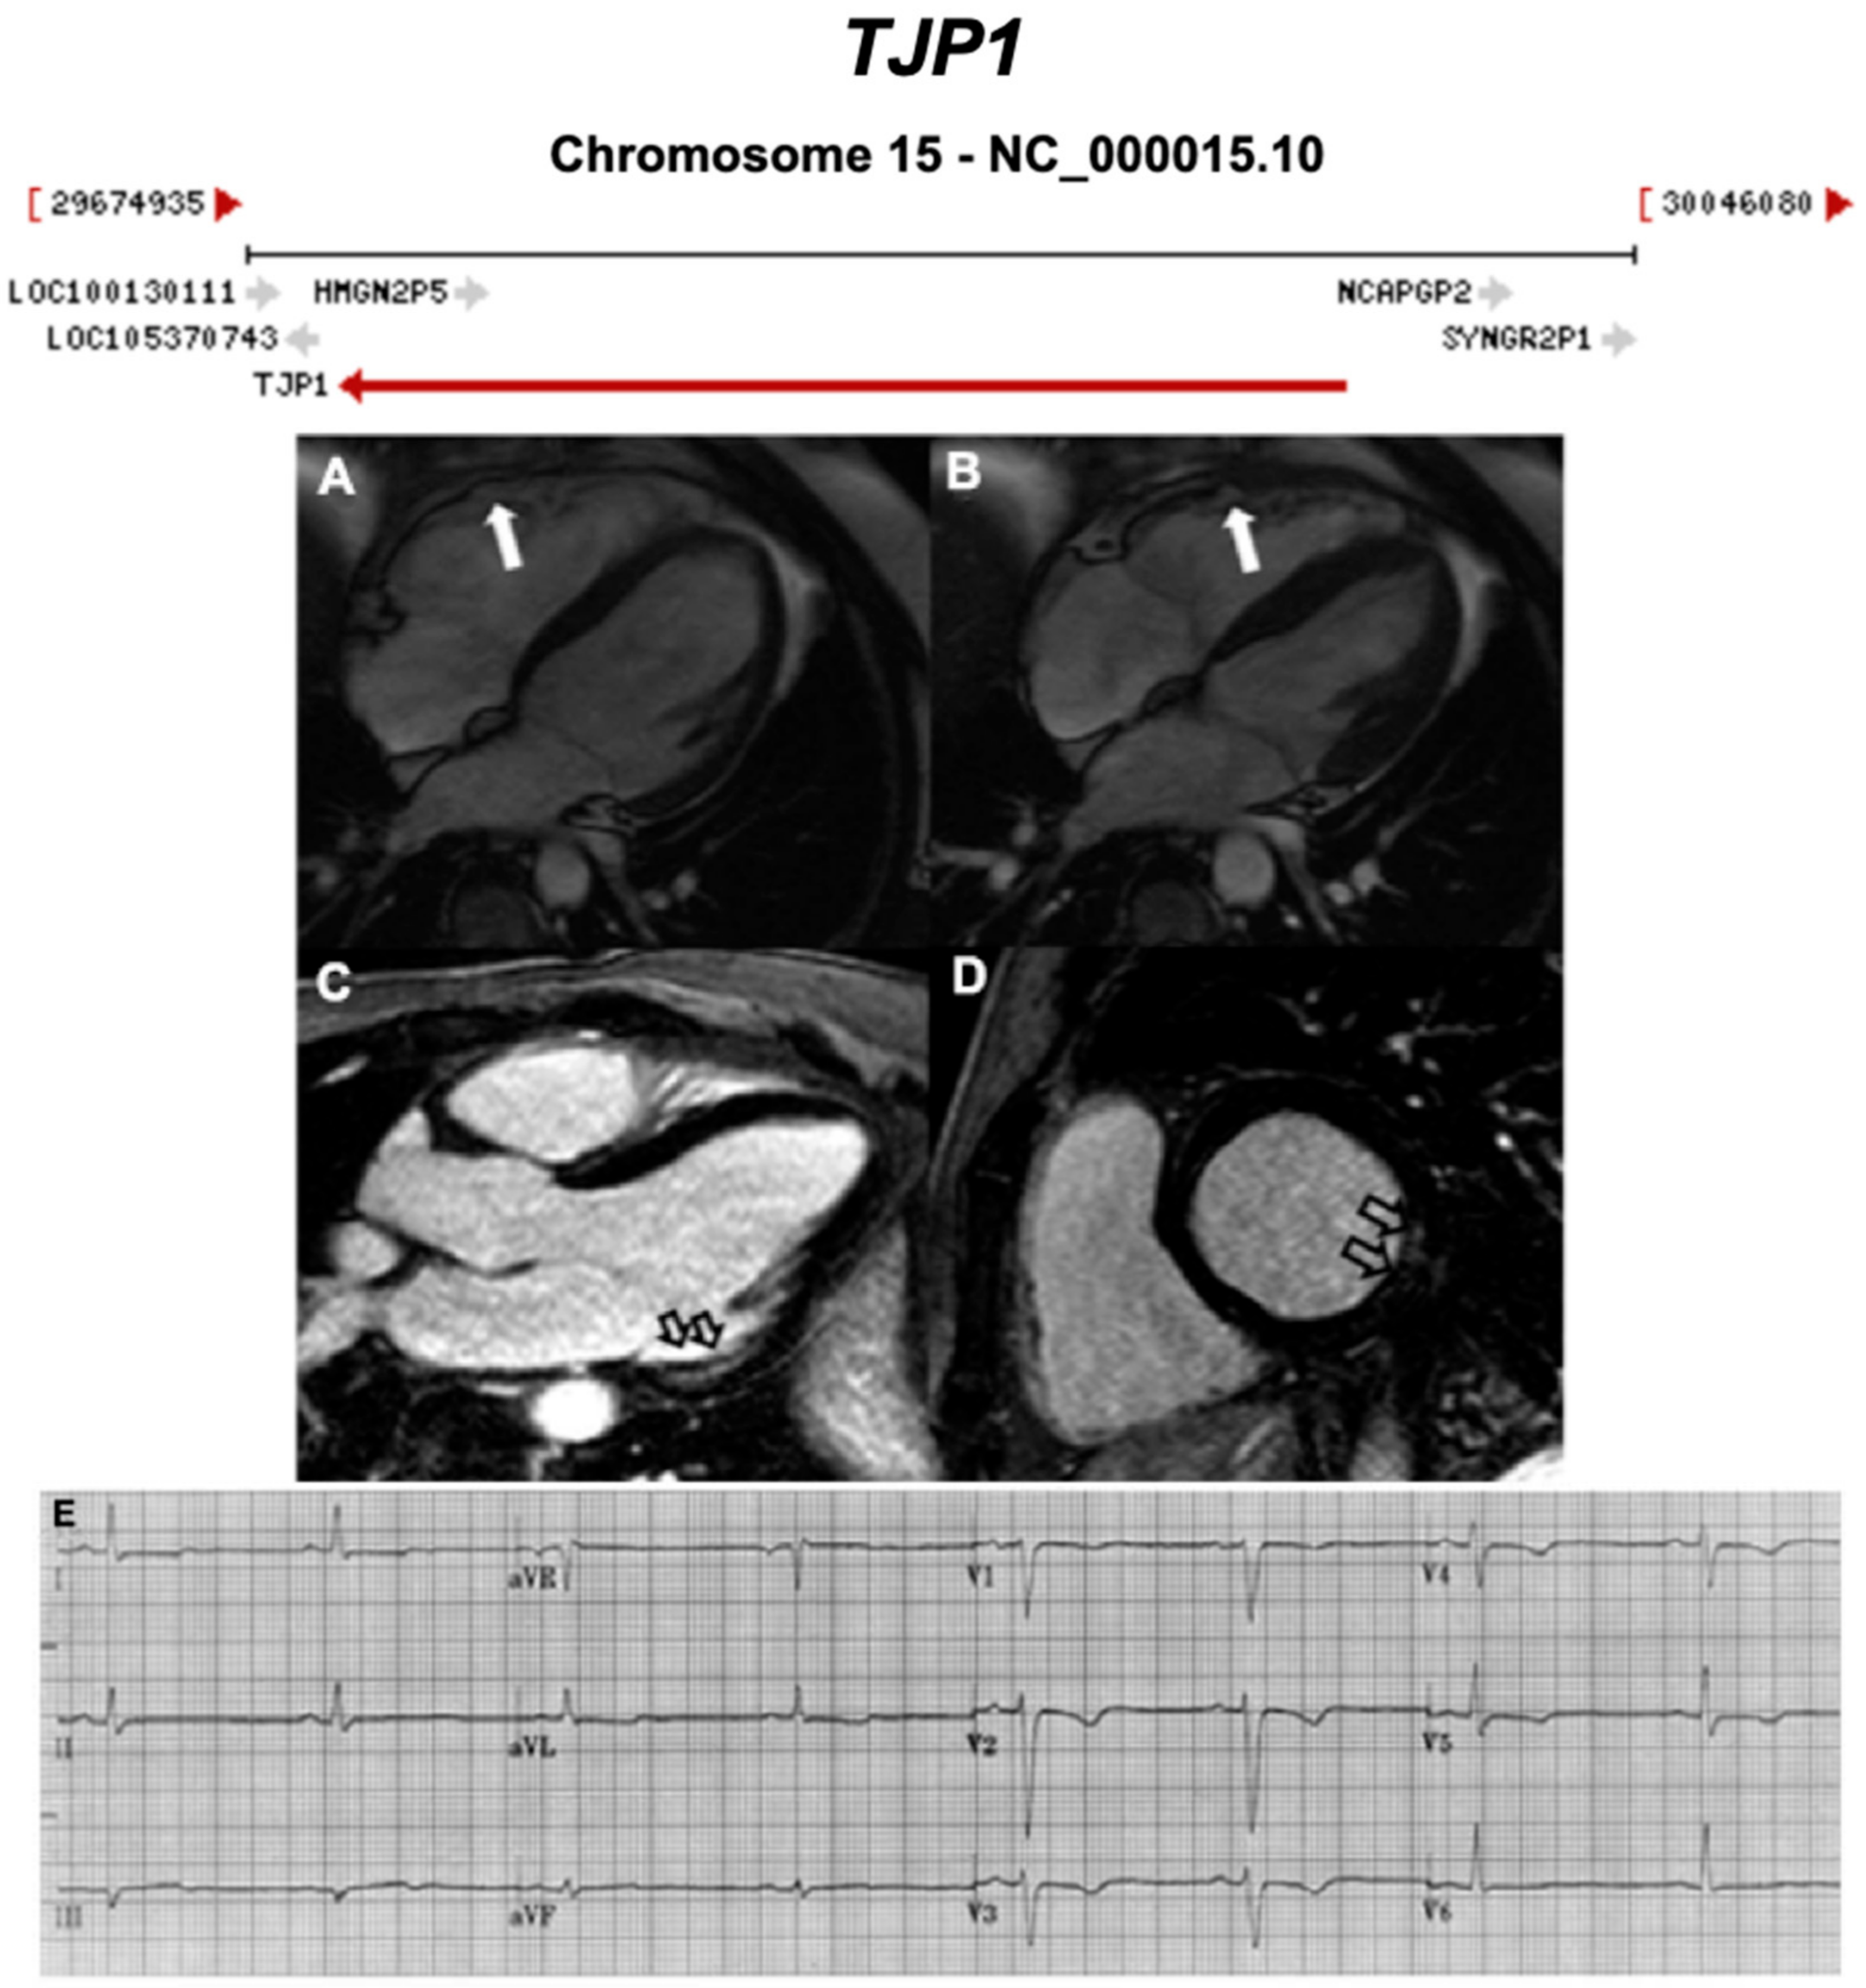

3.2.5. Tight Junction Protein 1 (TJP1) (Also Known as Zona Occludens 1) (Encoded by TJP1)

- De Bortoli, M.; Alex, V.P.; Poloni, G.; Calore, M.; Minervini, G.; Mazzotti, E.; Rigato, I.; Ebert, M.; Lorenzon, A.; Vazza, G.; et al. Whole-exome sequencing identifies pathogenic variants in TJP1 gene associated with arrhythmogenic cardiomyopathy. Circ. Genom. Precis. Med. 2018, 11, e002123. [Google Scholar] [CrossRef] [PubMed]

| TJP1 | Intercalated Disc | 0–4% [31] | AD | - | 15q13.1; 33 | Limited for ARVC | ||